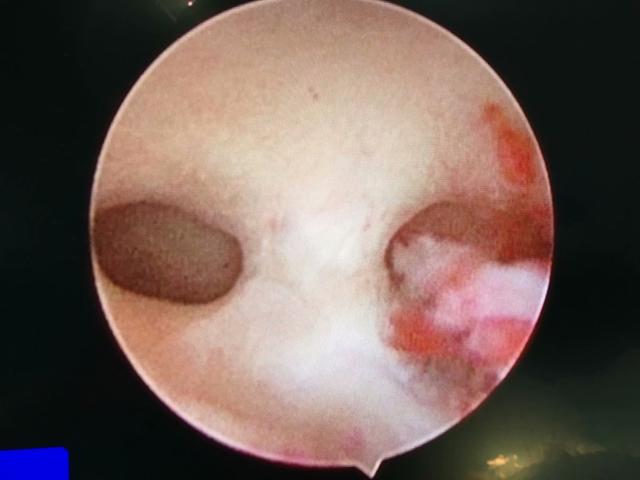

子宫内膜息肉

宫腔粘连